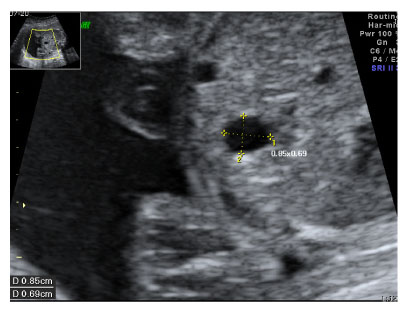

Fig. 1

Prenatal ultrasonogram showing cystic lesion (0.9 × 0.7 cm) in the stomach.

Fig. 1 Prenatal ultrasonogram showing cystic lesion (0.9 × 0.7 cm) in the stomach.